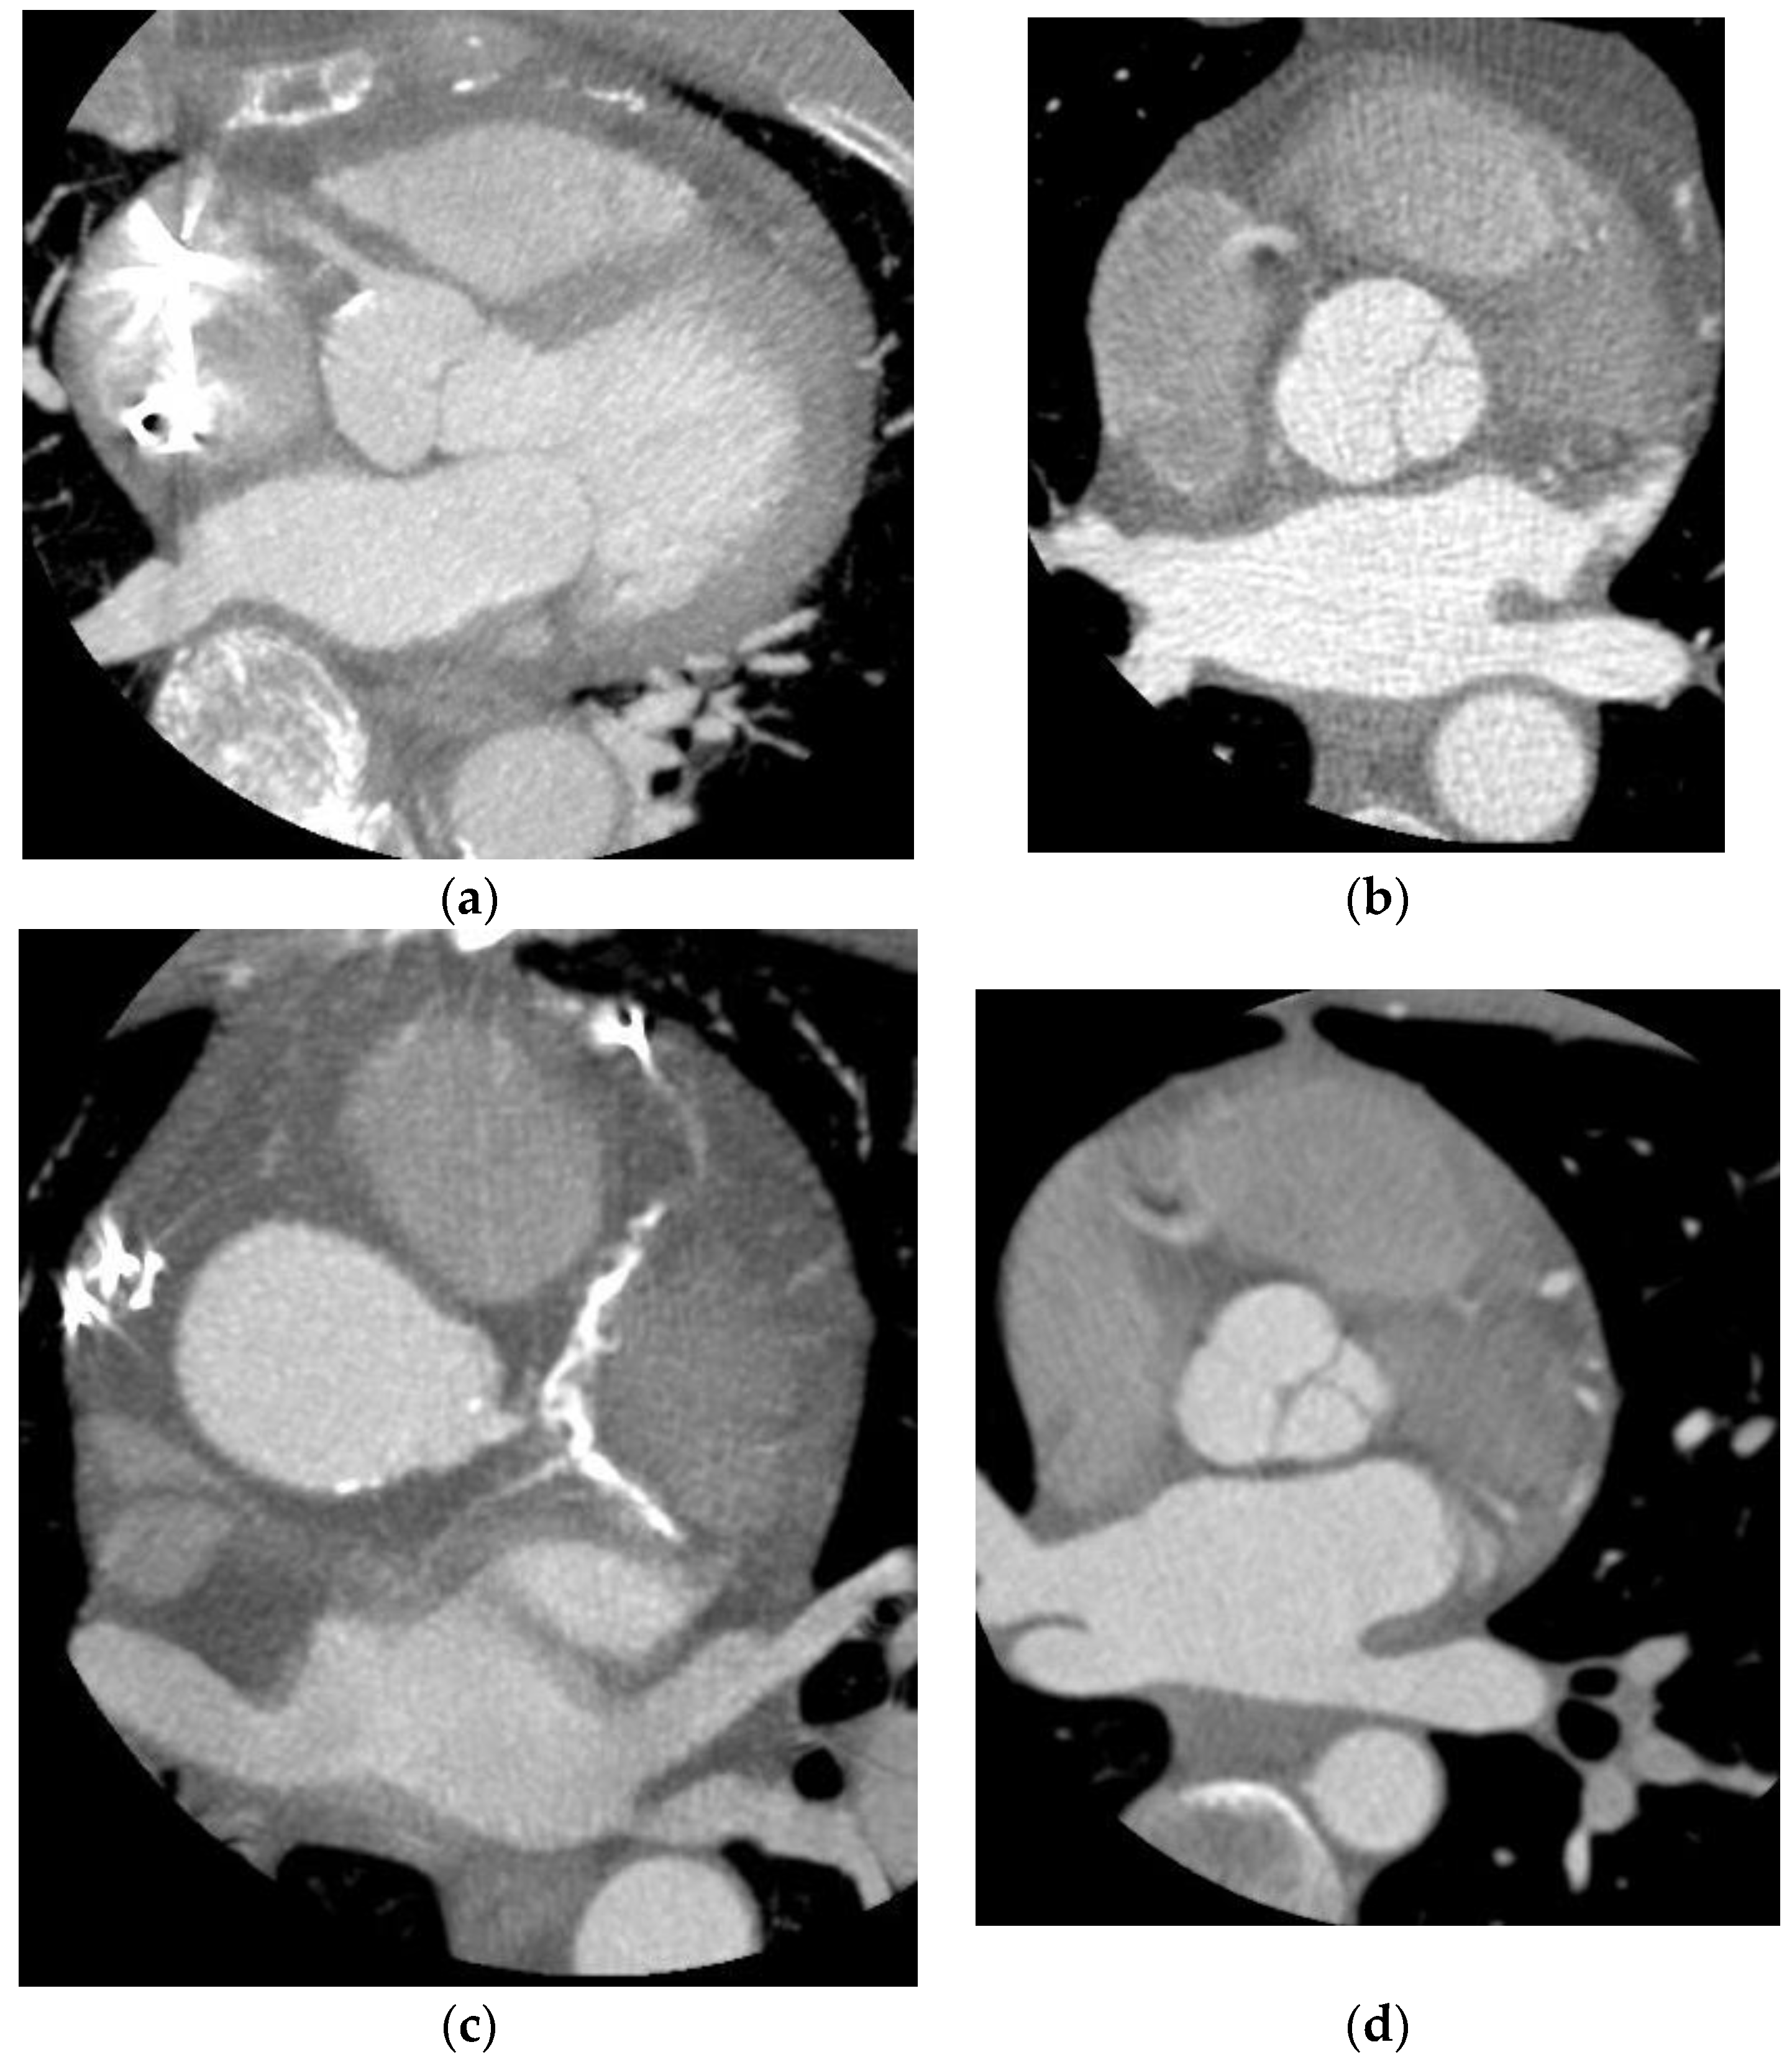

| CTA Image Quality | |||

| Excellent | 41 | 4 | 37 |

| Good | 20 | 10 | 10 |

| Fair | 13 | 9 | 4 |

| Poor | 30 | 29 | 1 |